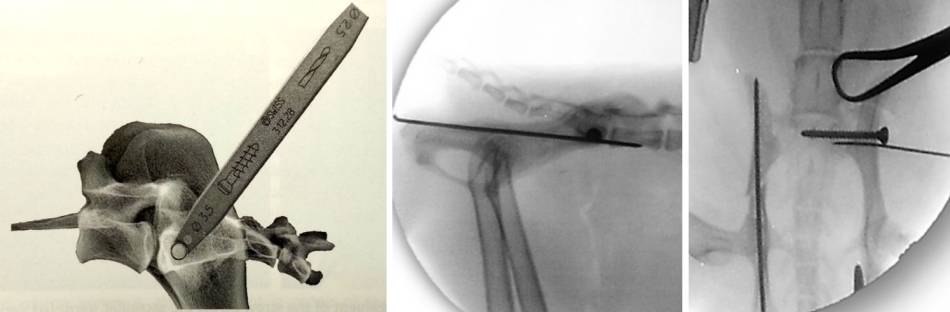

Minimalinvasive Reposition

- perfekte Seitenlage in Vakuummatratze (Proc. transversi superimposed)

- Reduktion der Fx

- cranial Dornfortsatz L7 angklemmen

- caudal Ilium / Sitzbein anklemmen

- Ilium nach caudal drücken

- nach Reduktion kleinen Pin setzen caudal davon wo die Schraube gesetzt wird

- Bohrung für Positionsschraube

- erst Pin setzen um für Bohrung vorzubereiten

- Hautschnitt und bis zum Ilium präparieren

- Bohrhülse über Pin stecken

- Pin entfernen und bohren

- Gleitloch bohren (vor OP schon Tiefe durch Ilium messen

- Schraube setzen

- Zugschraube 2,7 mm

- soll über mind. 60% des Sakrums gehen (Schraube ggr. kürzer als Bohrloch, evtl. Beilagscheibe nehmen)